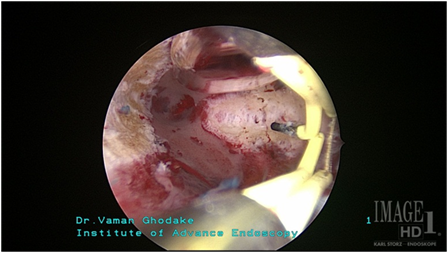

4) Asherman (गर्भाशयाचा आंतरभाग चिकटून बसणे) -

गर्भाशयाला जंतूसंसर्ग झालेमुळे गर्भाशयाची पोकळी आतून चिकटली जाते. त्यामुळे अंगावरुन फार कमी जाणे / फक्त डाग पडणे व गर्भधारणा न होणे अशा अनेक अडचणी निर्माण होतात. जर आपण ही पोकळी व्यवस्थित केली तर त्याचे फायदे होतात. घोडके हॉस्पिटलमध्ये अशा प्रकारच्या शस्त्रक्रियेमुळे बऱ्याच पेशंटना त्याचा फायदा झालेला आहे.

ashermanbeforeoperation

ऑपरेशनपूर्वी

ashermanafteroperation

ऑपरेशनंतर